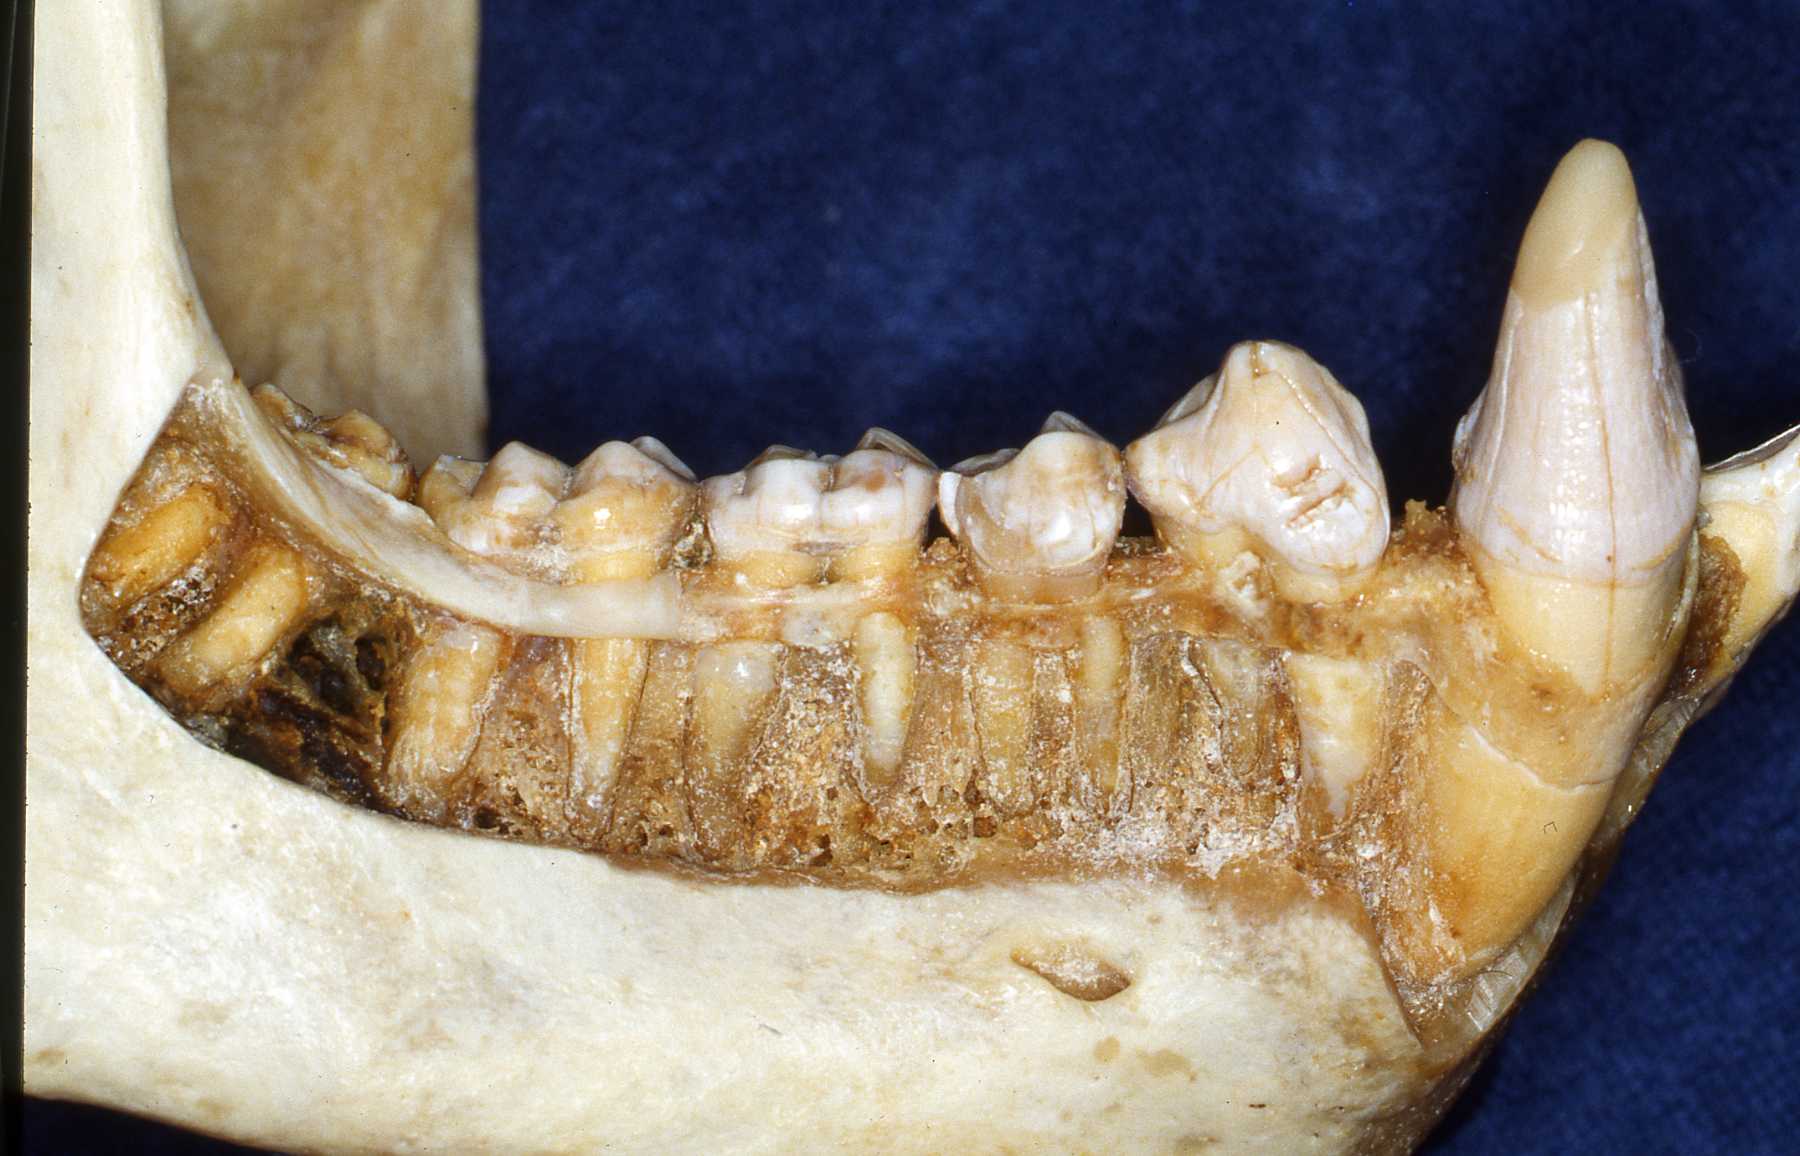

Use references such as those listed on this site. Radiographs of the particular species are very helpful. Skull and teeth collections are the optimum for preparation. I have encouraged accumulating a collection at our zoo and we have established an archive from animals that died at Milwaukee County Zoo. Over the years I established a relationship with the Milwaukee County Museum and the Zoological Museum at the University of Wisconsin, Madison. They receive the carcasses of our animals after pathologists evaluate them. Then the animals' skeletons are added to their or our collection.

The next most common pathosis encountered is periodontal disease. Again, improvement in diets has reduced this disease. I strongly believe that besides nutrients, diet texture is very important in optimizing oral health, minimizing periodontal disease. I believe that soft or pelleted foods that do not stimulate and challenge the dentition and periodontium may contribute to periodontal disease. Duplicating natural diets in this manner for diverse species is of course, not always possible, but zoos do make efforts to do so when they can.

In the gorillas and bonobos that were born and raised here at Milwaukee County Zoo, we have not had many periodontal problems. We have had adult gorillas come to us from other zoos with significant periodontal disease.

Most or our orangutans however, have had chronic, serious periodontal disease. All of our males have eventually lost all their teeth due to periodontal disease. That has not been the case with the females. We are not the only zoo that has had the chronic periodontal problems with orangutans. See Dr. Norm Stollers' paper: In the typical orangutan case that I have dealt with, there is not much accumulation of plaque or calculus. However, deep periodontal pocketing and bone loss progresses until the teeth become very mobile. I have not observed much bleeding in the most severe of these cases. We discussed preventive strategies and even tried chlorhexidine gluconate rinses to subdue the disease process. However, the orangs did not accept the products, probably due to the taste.

I believe that there is very likely some genetic component to the periodontal disease prevalence in our orangutan lineage. Most of them that we have had are crosses of Sumatran and Borneo genetic lines. And again, with what I have been able to learn about their wild diets is that it is very different than what can be offered in captivity in this part of the world.